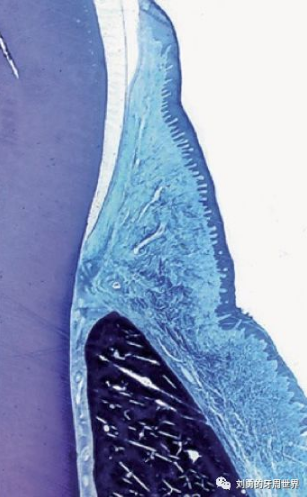

下面的這張切片也表明齦溝上皮是有釘突的。

但是再來(lái)看一張切片:

這張切片當(dāng)中,在齦溝上皮的區(qū)域似乎看不到明顯的釘突。